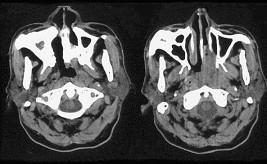

问题 男,64岁,间断性流鼻血1年余,近1个月加重,CT如图所示,最可能的诊断为()

选项 A.鼻咽部腺样体增生 B.鼻咽纤维血管瘤 C.鼻咽部恶性淋巴瘤 D.鼻咽部淋巴组织增生 E.鼻咽癌

答案 E